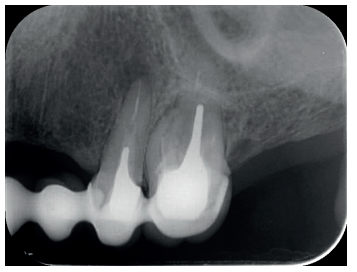

El paciente aporta como estudio radiológico una ortopantomografía (OPG), (Figura 1). Se realizaron radiografías periapicales (Figuras 2 y 3), así como exploración clínica incluyendo la valoración periodontal de los dientes afectados, sin observar profundidades de sondaje aumentadas que pudieran indicar la existencia de lesiones endoperiodontales.

Para confirmar el origen endodóntico y el tamaño de las lesiones se realizaron exploraciones tomográficas con espesor de corte de 75 micras mediante CBCT CS8100 (Carestream Dental® ) en las que se evidenciaron lesiones periapicales radiolúcidas a nivel de 12, 11, 21 (con afectación bicortical), 25 y raíces vestibulares de 26 (Figuras 4 a 8).

Por otra parte, las raíces vestibulares del 26 presentaban un tratamiento de conductos claramente deficiente, con subextensión de varios milímetros, así como conducto mesiopalatino (MP) omitido; por lo que se planteó al paciente la necesidad de reendodonciar dichas raíces, antes de realizar la microcirugía del 25 (Figura 9).